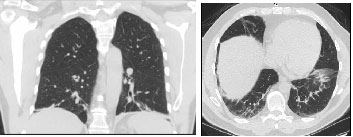

On examination the patient appeared exhausted and was not able to complete a full sentence without a pause. Respiratory rate was 26/min with an oxygen saturation of 94% on room air which dropped to 90% upon speaking. Physical examination was otherwise normal. Arterial blood gas revealed primary respiratory alkalosis. Complete blood count and Comprehensive Metabolic Profile were normal. Chest x-ray revealed mild interstitial opacities at the lung bases which were confirmed on CT scan of the chest [Table/Fig-1,2]. Cardiac brain natriuretic peptide and echocardiography were normal. Salicylate levels were normal. Evaluation of interstitial lung disease including urine legionella antigen, HIV antibody, ANA titer, hypersensitivity panel and fungal serologies were all negative.

Fluctuating skeletal muscle weakness is a cardinal feature of MG [6]. Characteristically, muscular exertion increases the myasthenic weakness. Thus, dyspnea may be fluctuating as in our patient causing further difficulty in diagnosis as the pulmonary function tests performed during remission may be normal. Interestingly the patient had dyspnea on immersion which can be specific for neuromuscular diseases [7]. It is likely due to diaphragmatic weakness affecting vital capacity and gas exchange. Our patient had basilar infiltrates on chest radiographs and CT scan that likely represented atelectasis. Patients with MG involving respiratory muscles frequently have atelectasis due to decreased diaphragmatic and respiratory muscle movement.

CT scan of the chest in coronal and transverse views respectively shows bilateral interstitial reticulonodular opacities at lung bases